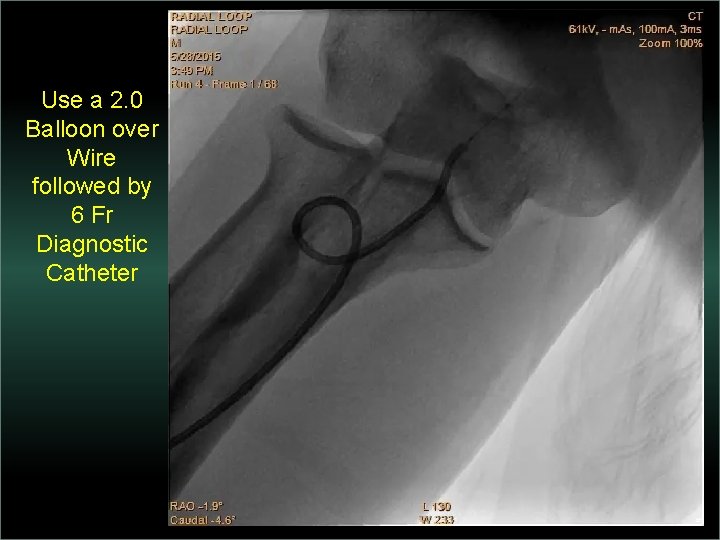

Transradial Interventions Difficult Anatomic Substrate Challenges and Solutions